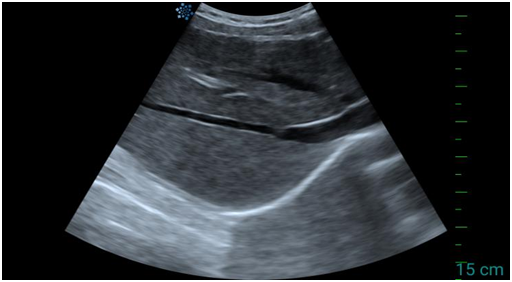

肝脏超声:你的“无声医生”能看到什么?